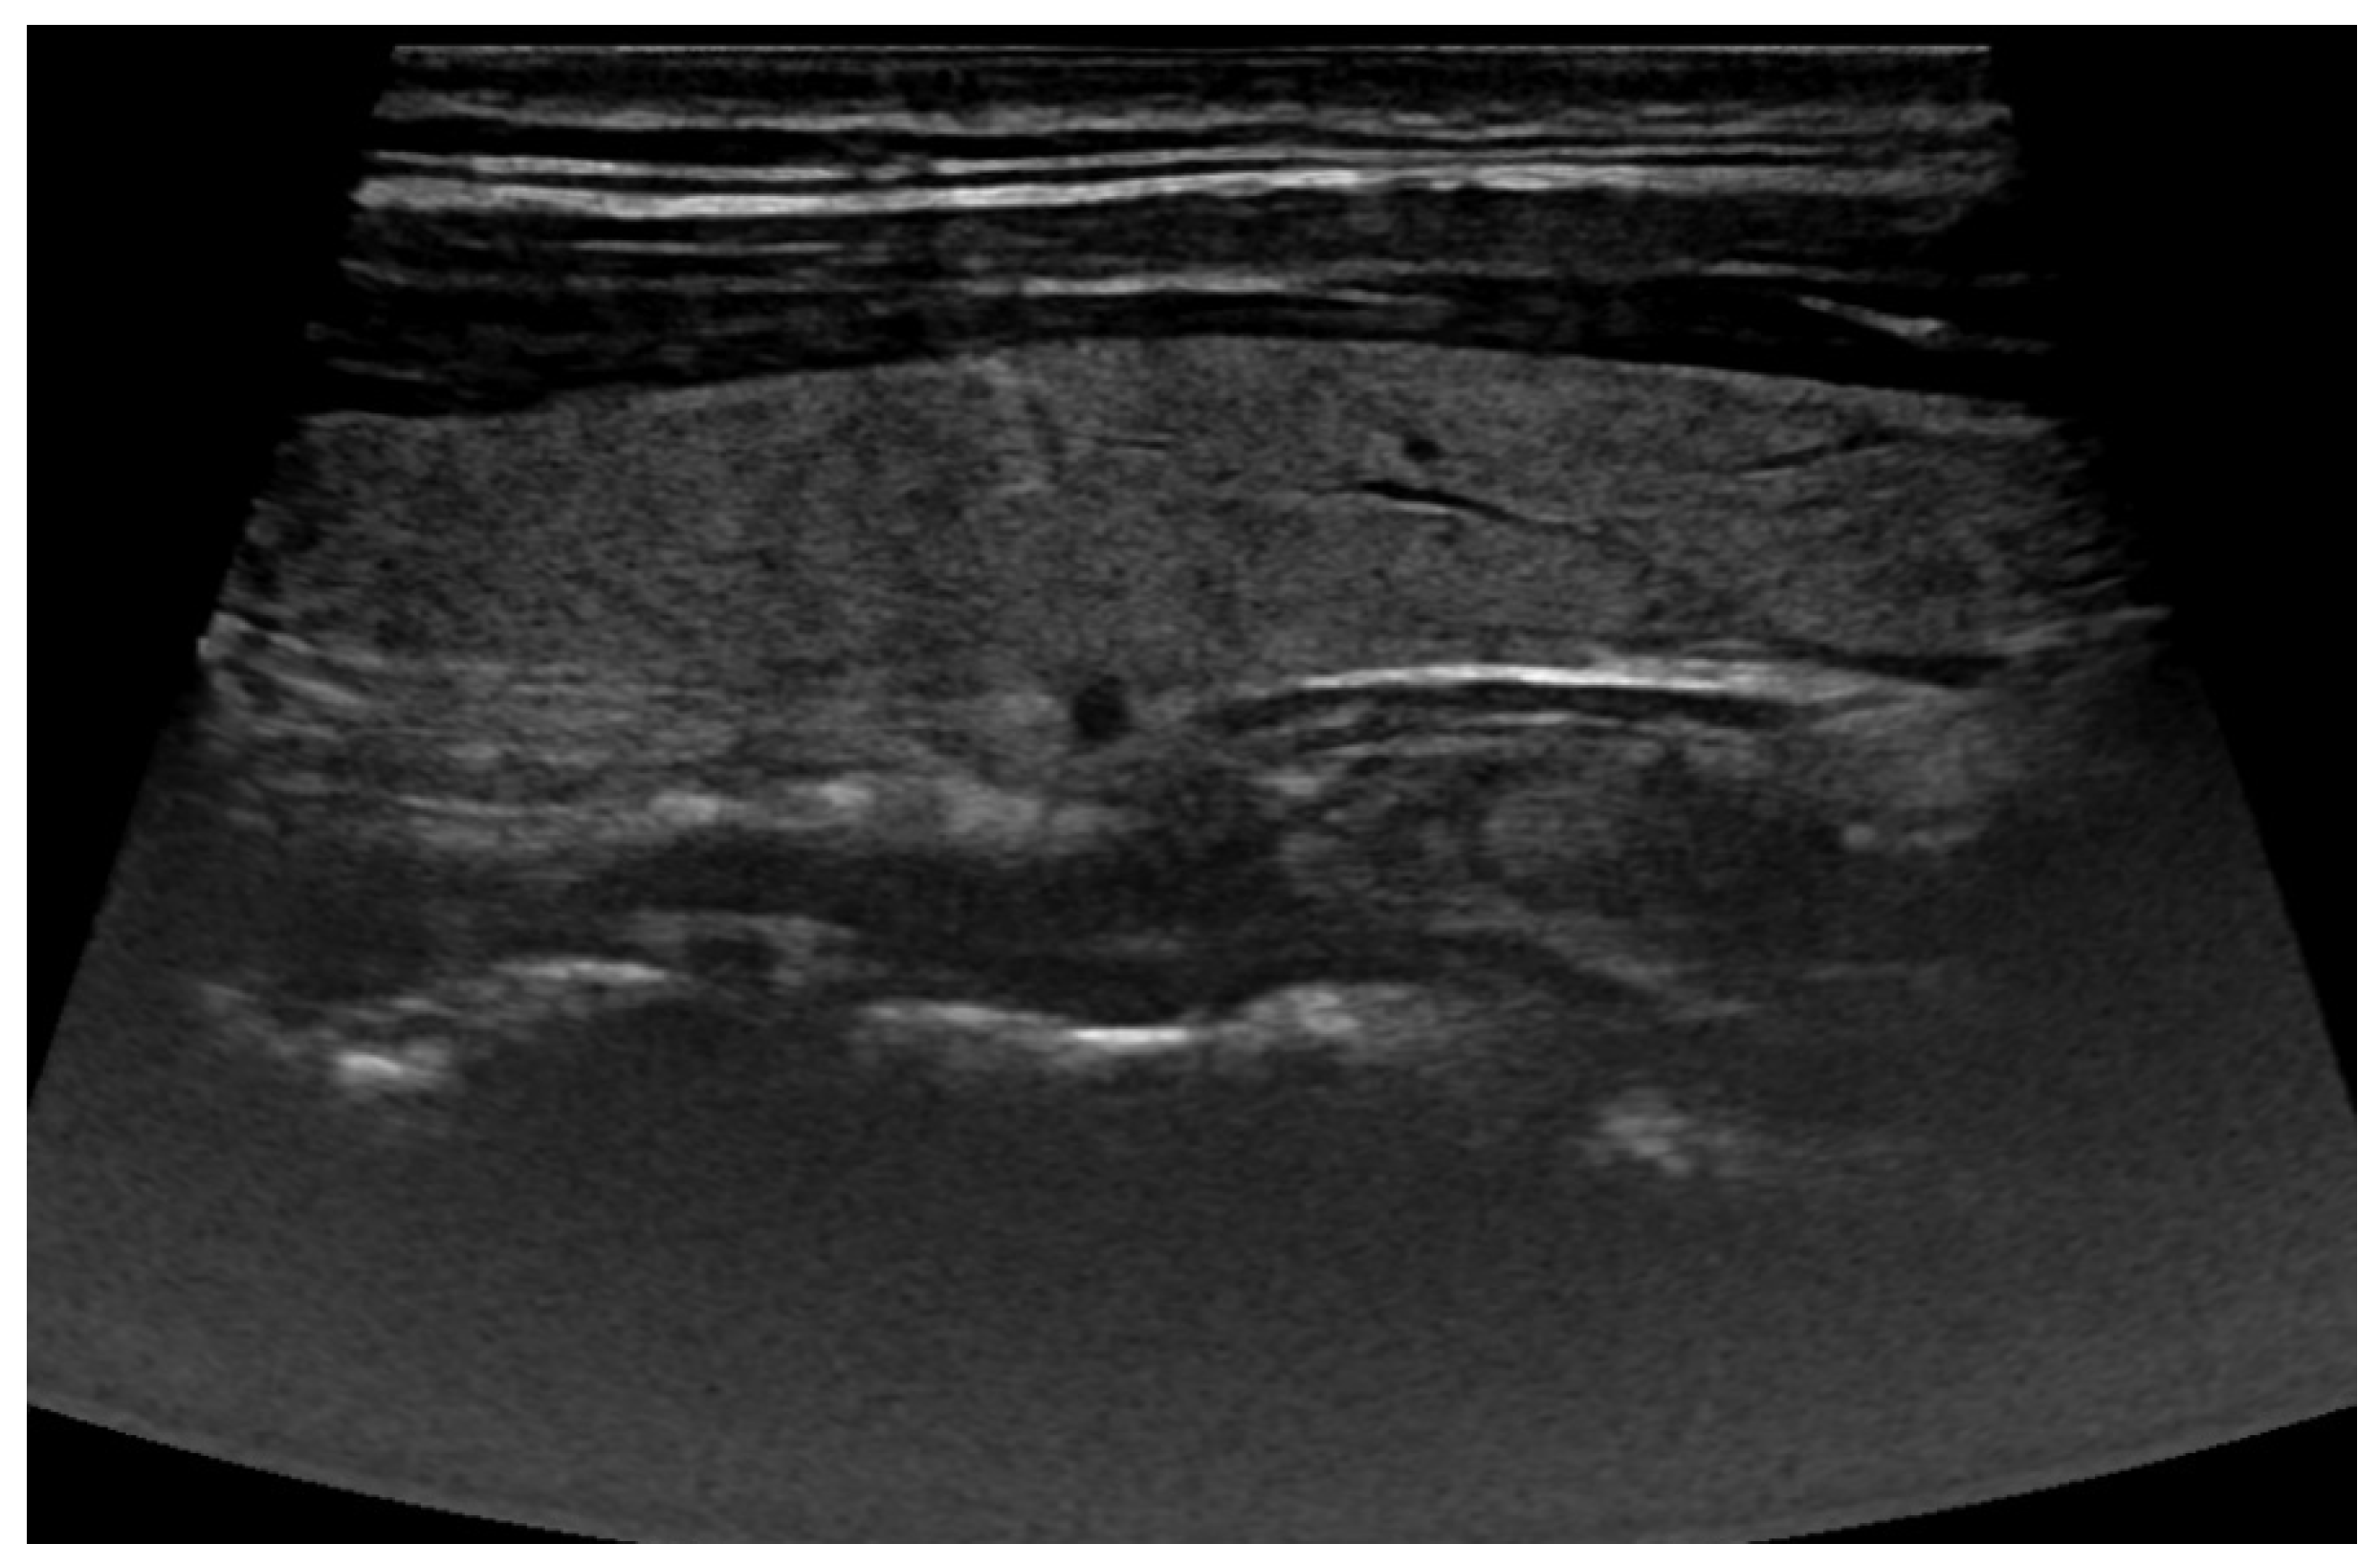

2.1. Ultrasound Images

2.1.1. The Data

3.1. Thyroid Nodule Diagnosis Based on Ultrasound Images: Binary Classification Problem Solved Using Convolutional Neural Networks